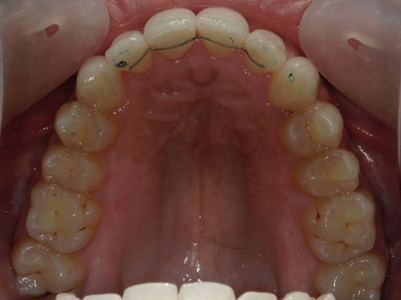

Après traitement orthodontique et réalisation d’une attelle coulée collée (courtoisie Dr Patrick Fournier)